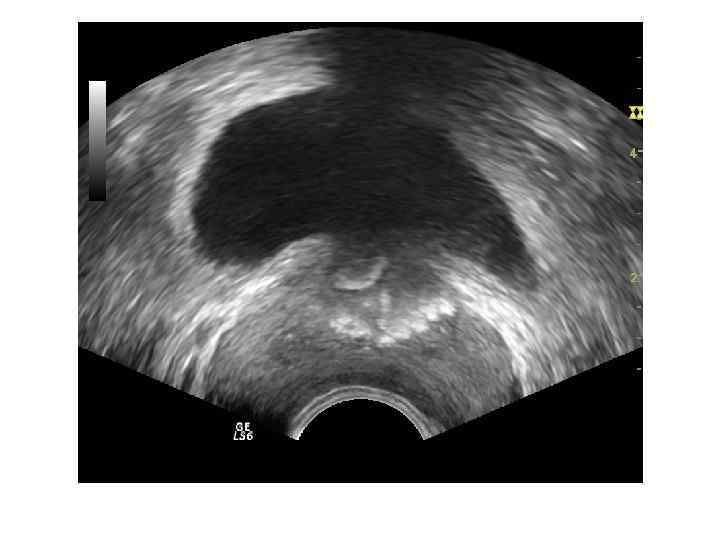

ДГПЖ Доброкачественная гиперплазия простаты – заболевание , характеризующееся гиперплазией железистых и стромальных элементов ткани предстательной железы. Основными источниками ДГПЖ являются переходные зоны и зона периуретральных желез.

Если происходит преимущественный рост переходных зон, образуются латеральные доли. Зональная анатомия предстательной железы при ДГПЖ. При ДГПЖ увеличивается объем переходной зоны (Tz), размеры центральной зоны (Cz) и периферической зоны (Pz) уменьшаются. Vm — семенной бугорок, А — фибромускулярная строма.

При росте периуретральных желез (ограниченных препростатическим сфинктером) образуется средняя доля.

При ДГПЖ меняются форма, размеры, структура и соотношение частей железы. Форма становится шаровидной или неправильной с выбуханием контура в просвет мочевого пузыря. При росте переходных зон происходит значительное увеличение размеров, но это не приводит к выраженной обструкции уретры. При росте периуретральных желез простата увеличена незначительно, но происходит сдавление уретры выбухающей средней долей. Структура гиперплазированных узлов неоднородная, часто с дегенеративными изменениями ( кисты, участки склероза, кальцификаты).